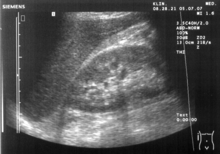

Ultrasonographic view of the abdomen demonstrating fluid within Morison's pouch.

Morison's pouch with fluid present (at red arrows).